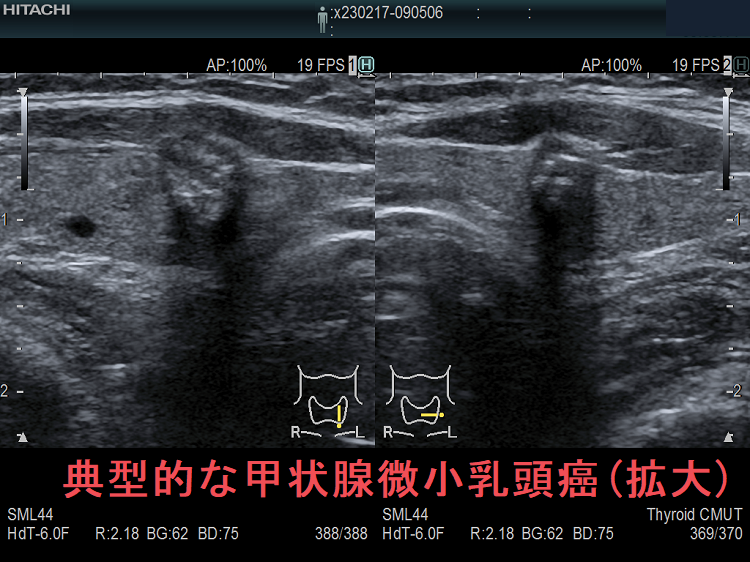

甲状腺微小乳頭癌は超音波エコー検査でどう見えるか①極めて低エコー(不整形、境界不明瞭、辺縁粗雑)で橋本病(慢性甲状腺炎)の破壊による変性と鑑別難②環状高エコー被膜③石灰化(微細石灰化・斑点状・卵殻状石灰化は通常型と同じ、破片状・塊状石灰化が多い)。甲状腺微小乳頭癌で反回神経浸潤(Ex1,Ex2)が術前・術中に見つかるのは、腫瘍が背側かつ気管寄りの場合。甲状腺超音波(エコー)では腺腫様結節にしか見えず、エラストグラフィーで軟らかく、10mmに満たないが穿刺細胞診すると甲状腺微小乳頭癌の事がある。女性の30人に1人の割合で甲状腺乳頭癌が存在。

甲状腺微小乳頭癌は超音波(エコー)検査でどう見えるでしょうか?

- 最も一般的なのは、真っ黒な(極めて低エコー)、いびつな形(きれいな円形・楕円形をしていない、不整な形)をした、境界がはっきりしない(境界不明瞭)、辺縁粗雑な腫瘤

[以上の条件を満たす10mm未満の腫瘤は、不整な低エコー領域として見えるため、特に橋本病(慢性甲状腺炎)では甲状腺組織の破壊による変性と鑑別が難しい。]